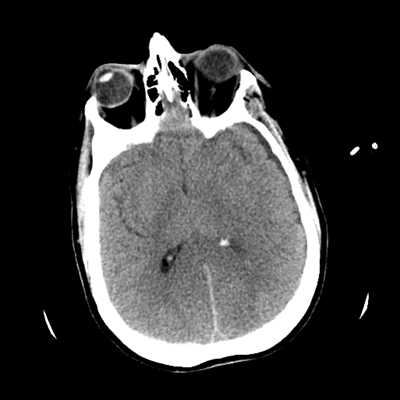

The patient goes down to CT. The following images are obtained. The subdural fluid collection is stable, as is the ventricular caliber.

NCHCT

Starting with the non-contrast head CT, we can appreciate that there's actually not much residual subarachnoid blood at all; it's essentially all resorbed already (and cleared through the EVD). The ventricular caliber is stable. With the CTA head (for convenience's sake, the MIPs were shown), it's subtle, but we can see that the PCAs on each side are not as smooth and regular. The right MCA, starting at the bifurcation, also becomes narrower. This is [radiographic] vasospasm. Now, looking at the CT perfusion-- specifically, the Tmax (MTT) map that were selected-- there's clearly some abnormality within the bilateral cerebellar hemispheres and occipital lobes. Not a lot, but it's there. Delving further into this map, we can appreciate that the areas of abnormality are mainly green, signifying that these areas have Tmax > 6 seconds. This is the threshold that is specific, not sensitive, for vasospasm.

Putting this all together, we have thus identified radiographic vasospasm with the vessel imaging, with perfusion abnormalities that are concordant with it. Does the area of vasospasm and hypoperfusion correlate with the patient's clinical exam?

Yes! It does. The patient had a decline in level of consciousness with diffuse loss of motor function. This does correlate to the basilar territory. (Alternatively, bilateral MCA vasospasm could also be responsible, reminding us that a decline in consciousness could technically be focal/multifocal.) Thus, we can say that this patient does have clinical vasospasm. Whether this will develop into irreversible DCI remains to be seen; at least, the non-contrast head CT and the other portions of the CT perfusion (not shown) currently don't [yet] suggest infarction.